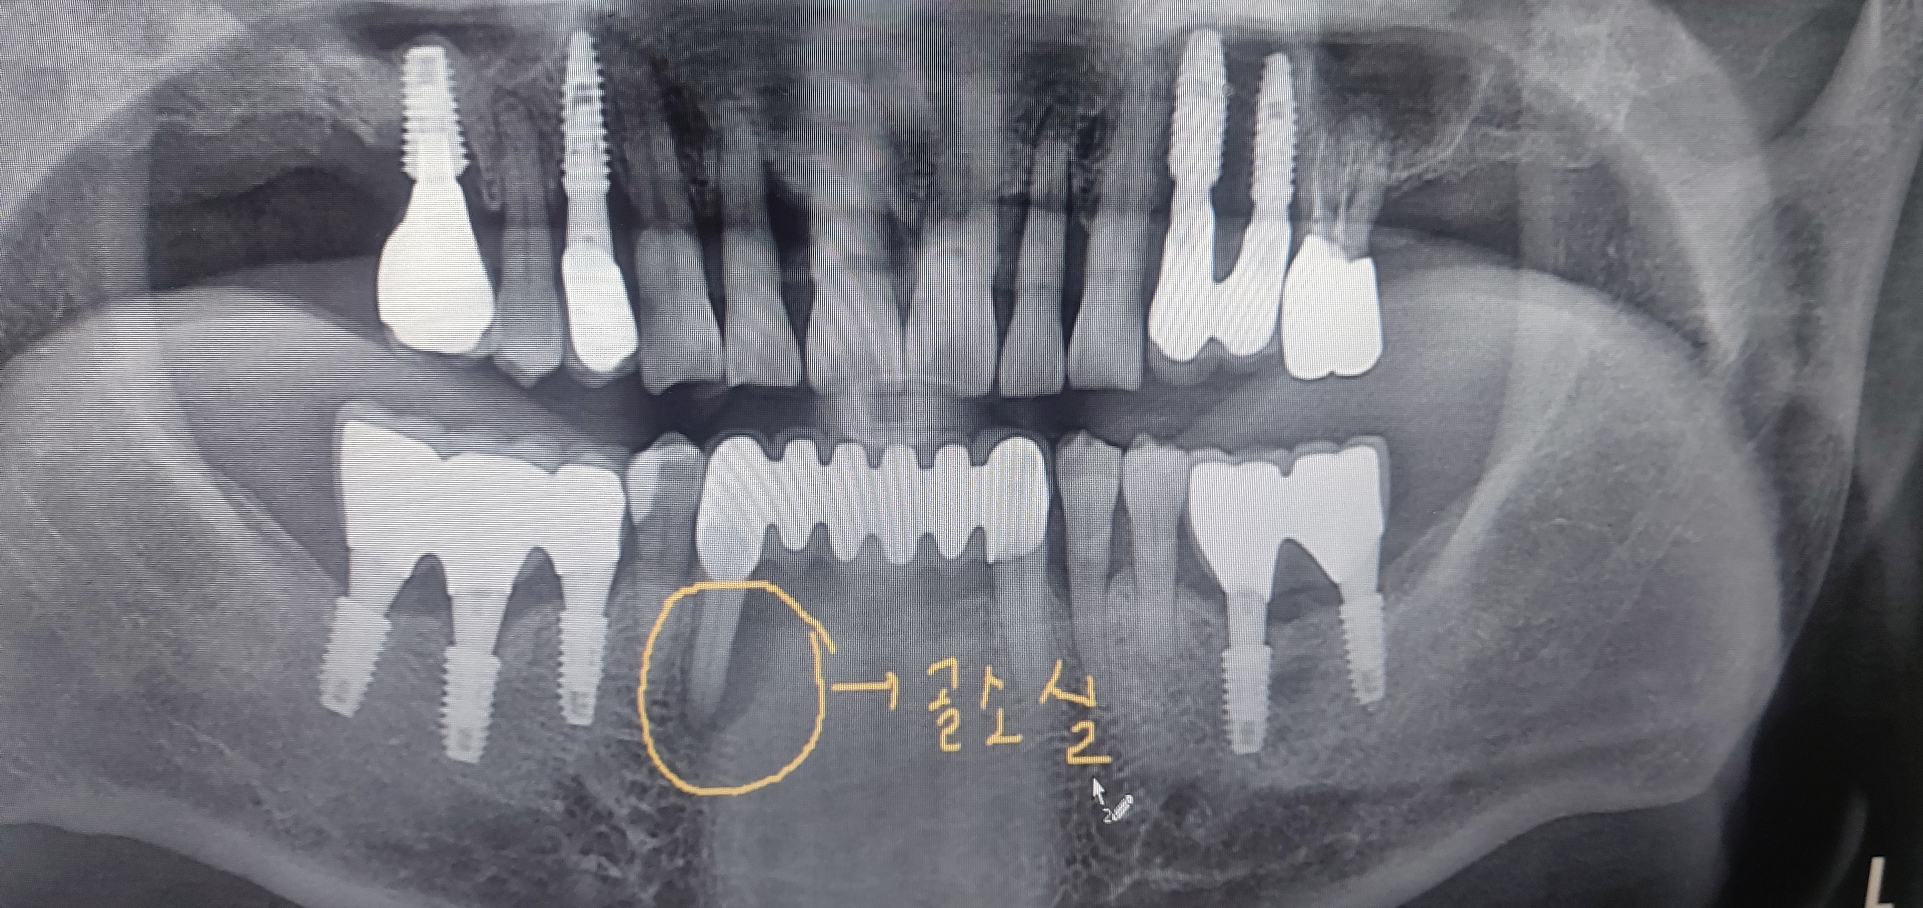

오른쪽 아래 송곳니 부위의 염증이 너무 심하여 잇몸 주위로 많이 부어 있는 상태였고 환자분이 발치 후 보철상담을 하러 오신 경우였습니다.

워낙 젊으신 50대 초반의 남자 환자분으로 앞니 없이 가철성 임시치아로 지내시는 것에 대한 불편감과 여러번 수술에 대한 피로도를 말씀하셔서

수면마취후 수술을 권해 드렸고 즉시 부하로 최대한 빨리 5일정도면 예쁜 고정성 임시치아가 가능하다고 말씀드렸습니다.